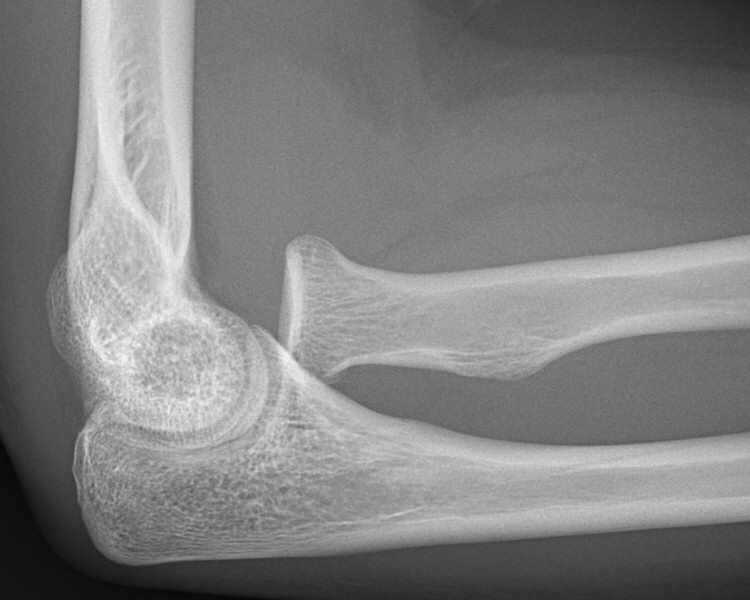

På röntgenbild ska radius längsaxel normalt gå centralt igenom capitellum humeri i både frontal- och sidobild av armbågen. Vid luxation:

Luxerad caput radii, ingen fraktur i ulna, på andra bilden reponerad och gipsad